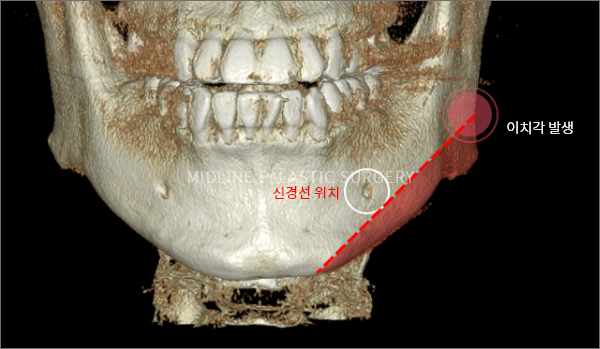

사각턱축소술

뼈의 절단면 비교

MIDLINE PLASTIC SURGERY

올라운드 사각턱수술

한 번에 최대 길이의 곡선 형태로 절골하여

곡선의 형태로 자연스러운 라인

※ 개인에 따라 절골 면적과 길이가 다르기 때문에 상담을 통해 수술계획을 세우는 것이 중요합니다.